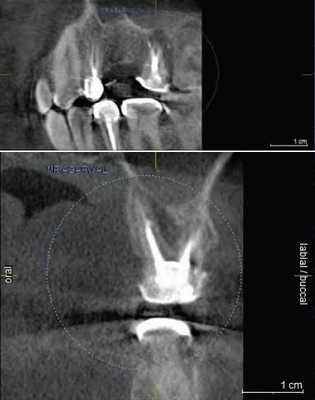

(Слева) На периапикальных рентгенограммах визуализируются четко очерченный рентгенонегативный тракт проводника зу6а (ПЗ) связанный с верхним краем коронки постоянного клыка нижней челюсти справа, мигрировавшего на противоположную сторону. Тракт доходит до альвеолярного гребня возле оставшегося временного клыка справа.

(Справа) На корональной (справа) и аксиальной (слева) КЛКТ визуализируется ПЗ, идущий от коронки импактного постоянного клыка нижней челюсти справа до альвеолярного гребня с язычной стороны от сохранного временного клыка.

2. Рентгенография проводника зуба:

• Интраоральная рентгенография:

о Четко отграниченный рентгенонегативный тракт, идущий от коронки импактного зуба до обычной области прорезывания в альвеолярном отростке

3. КТ проводника зуба:

• КЛКТ:

о Гиподенсный тракт с кортикальной пластинкой, идущий от зубного фолликула импактного зуба до альвеолярного отростка

4. Рекомендации по визуализации:

• Лучший метод визуализации:

о Периапикальная рентгенография

о КЛКТ